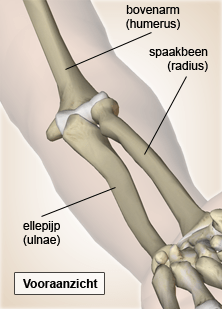

Elleboog